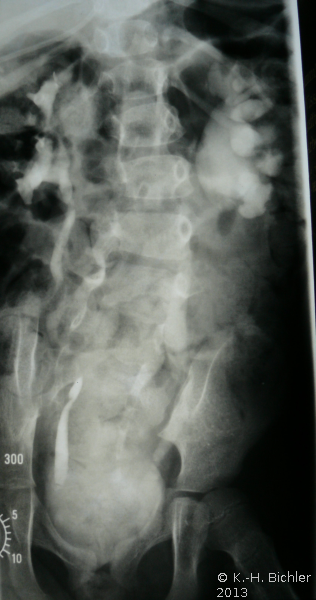

Bei einem 8-jährigen Mädchen mit MMC, ventriculo-peritonealem Shunt und rezidivierenden Harnwegsinfekten ergab die urologische Untersuchung mit Sonographie, AUR, MCU und Urodynamik einen Harnstau II. Grades der linken Niere mit Verplumpung des NBKS (AUR), glatte Abflussverhältnisse rechts (Abbildung 15), VUR links (Abbildung 16b).

Die Urodynamik zeigte eine komplette, nicht ausgeglichene obere motorische Läsion (Abbildung 16a).

Deutliche herabgesetzte Compliance der Harnblase, Wandumbau der Harnblase, eingeschränktes Harnblasenfüllungsvolumen und erhöhter Harnblasendruck. Im Isotopen-nephrogramm:

Nierenfunktion: 85% rechts, 15% links.

Diagnose: Obere motorische Läsion, Low Compliance Blase bei MMC, VUR links mit Refluxnephropathie